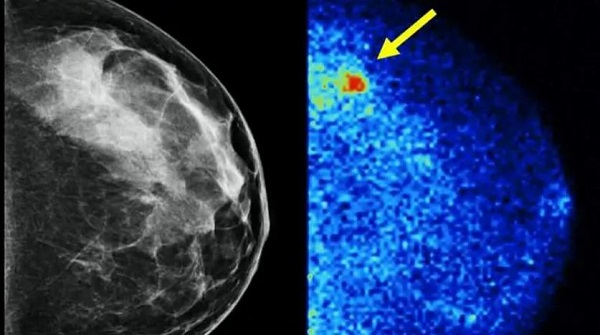

Mayo Clinic Health System discusses advancements in breast cancer screenings

October 1, 2024 – MANKATO, Minn. ― Since the 1970s, mammograms have been shown to reduce the risk of dying of breast cancer and have saved countless lives.

“In the decades since early mammography was established, the emergence of new screening options go well beyond traditional mammography and have made great advancements in early detection,” says Tara Krosch, M.D., regional vice chair of clinical practice for surgical specialties, Mayo Clinic Health System in Southwest Minnesota. “As we all know, early detection is key to the best patient outcomes, so it’s vital that patients get their annual screenings.”

In recognition of Breast Cancer Awareness Month, Mayo Clinic Health System is encouraging people to talk to their healthcare team about the right screening options for them and to get those screenings scheduled. Here’s what you need to know about the most common options and which might be best for you.